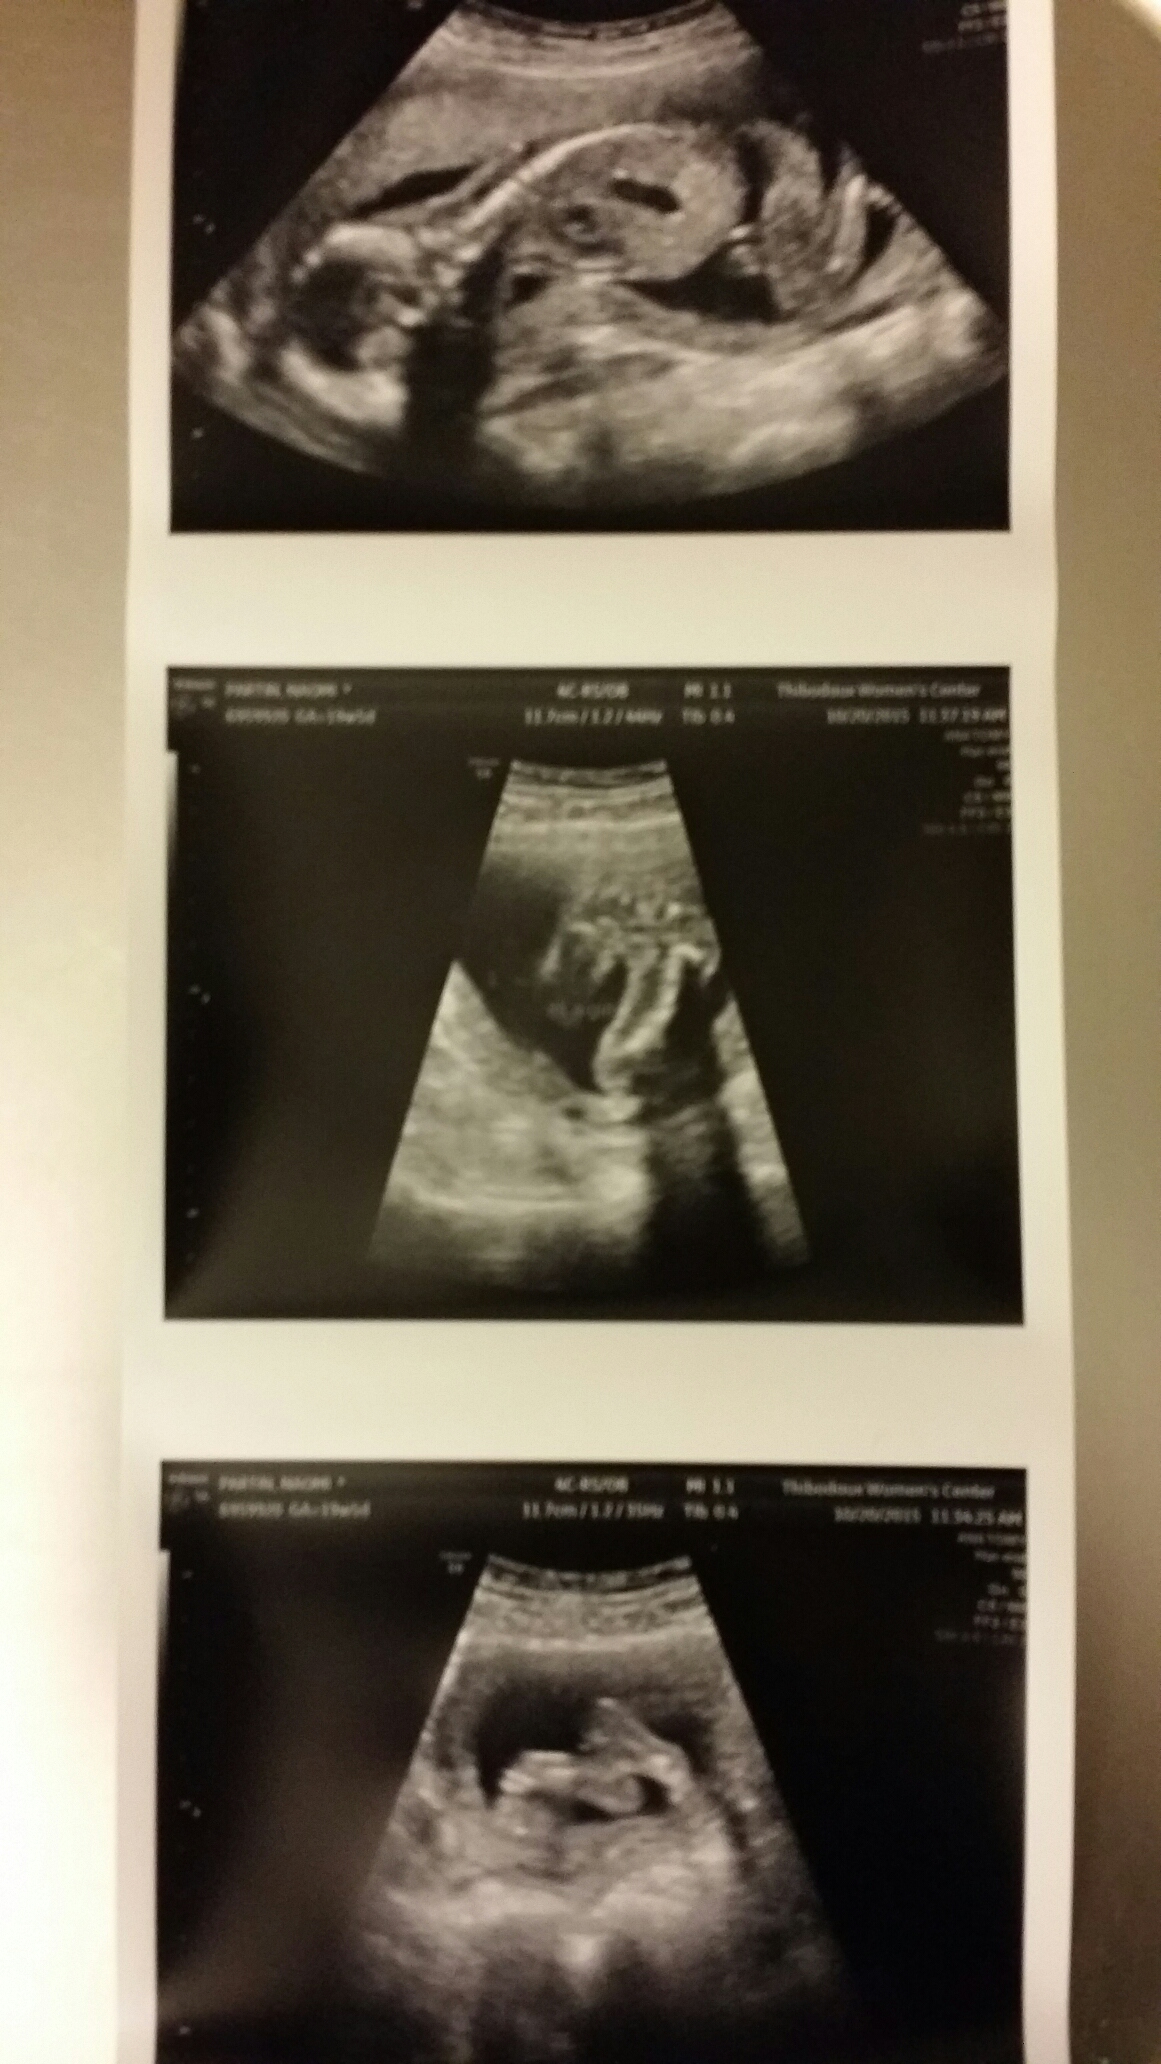

Has anyone needed a follow up anatomy scan? The tech said she couldn't get the spine or all images of the heart. I didn't see the doctor, but I'm due back in 4 weeks for a follow up, should I be worried or does this happen sometimes?

So i tried to search the Board but wasn't finding what I was looking for.... Has anyone needed a follow up anatomy scan? The tech said she couldn't get the spine or all images of the heart. I didn't see the doctor, but I'm due back in 4 weeks for a follow up, should I be worried or does this happen sometimes?

I have to go back 11/11 for a follow-up scan. Baby is transverse lying on its tummy, and the tech was not able to get a good profile pic. Plus she discovered I have a low-lying placenta, so we have to make sure that moves up. AND I didn't get to find out the sex either, because of baby laying the way he/she was. I'm hoping to find out this next ultrasound- fingers crossed baby uncrosses its legs!